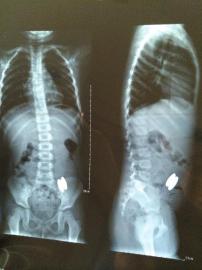

醫院X光檢查顯示,這兩塊磁性橄欖球長2.8厘米、直徑0.8厘米,它們隔著彎曲的小腸壁吸附在了一起,導致無法自行排出體外,靜靜父母準備將孩子送到重慶進行手術。醫生提醒說,靜靜體內的磁鐵應盡快取出,否則有較大危險,容易引發腸道損傷,嚴重可能導致穿孔或者壞死。

但這時麻煩就來了,進入小腸前,兩塊磁性橄欖球并不在一起,進入小腸后,它們隔著彎曲的小腸腸壁吸附在了一起,這就導致無法自行排出體外。經過多次X光檢查顯示,到8月10日,已經36天,但它們在小腸中的位置基本沒有變化。